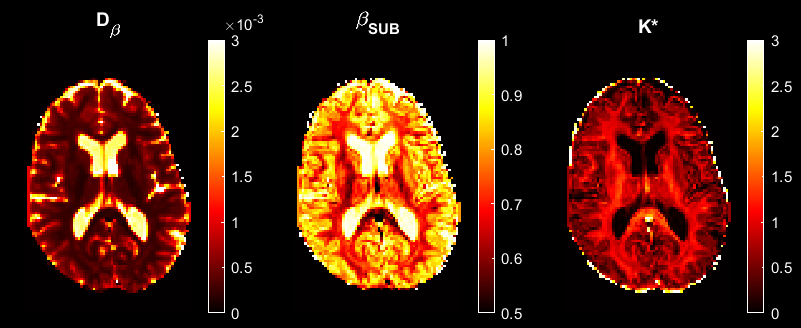

- establishing mathematical links between the prevalent diffusional kurtosis imaging (DKI) model and our sub-diffusion model, which provides a new and more accurate way of estimating diffusional kurtosis;